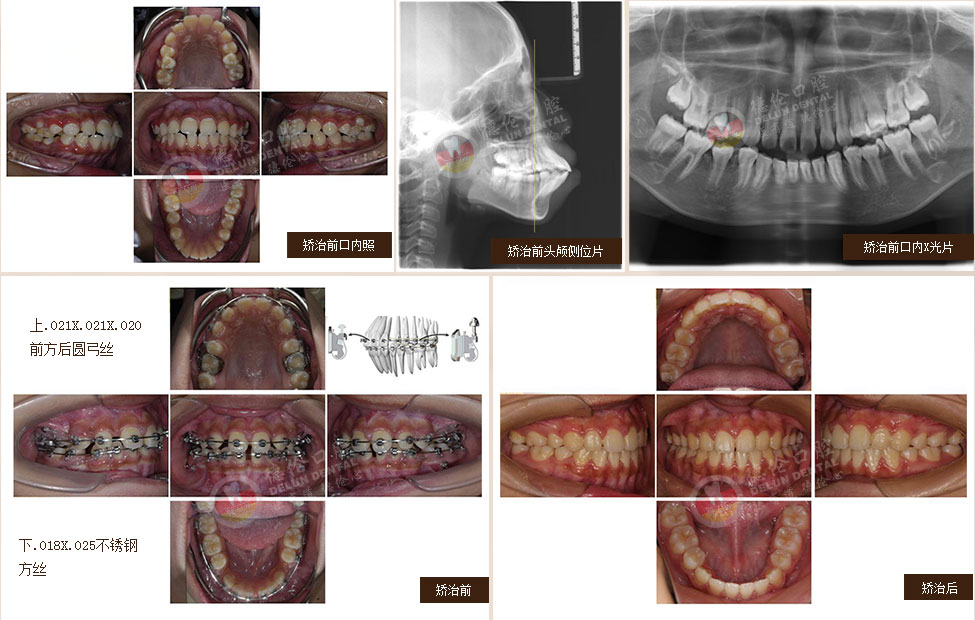

• 女:24歲

癥狀:牙列不齊、下頜第二、第三磨牙水平阻生,左側磨牙鎖牙合

矯治方法:拔除上頜及右下第一雙尖牙,左下第二雙尖牙以及2個下第三磨牙